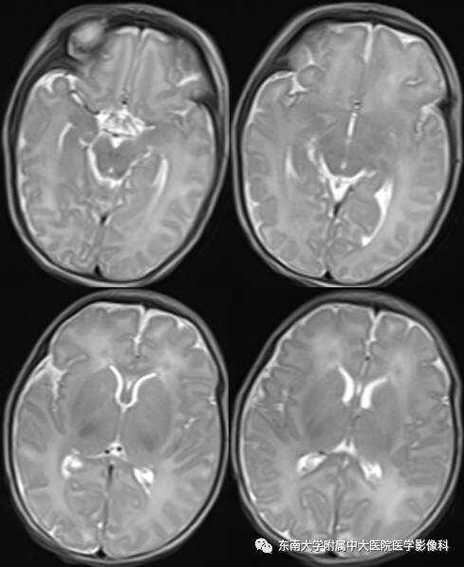

(图片来源网络,侵删)